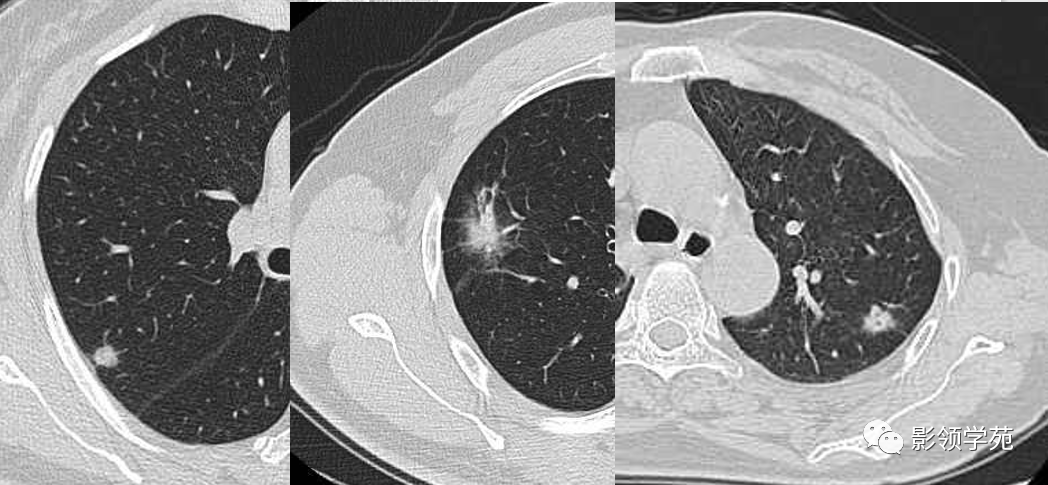

肺泡癌影像诊断与鉴别诊断

图片尺寸622x383

图片尺寸1048x485